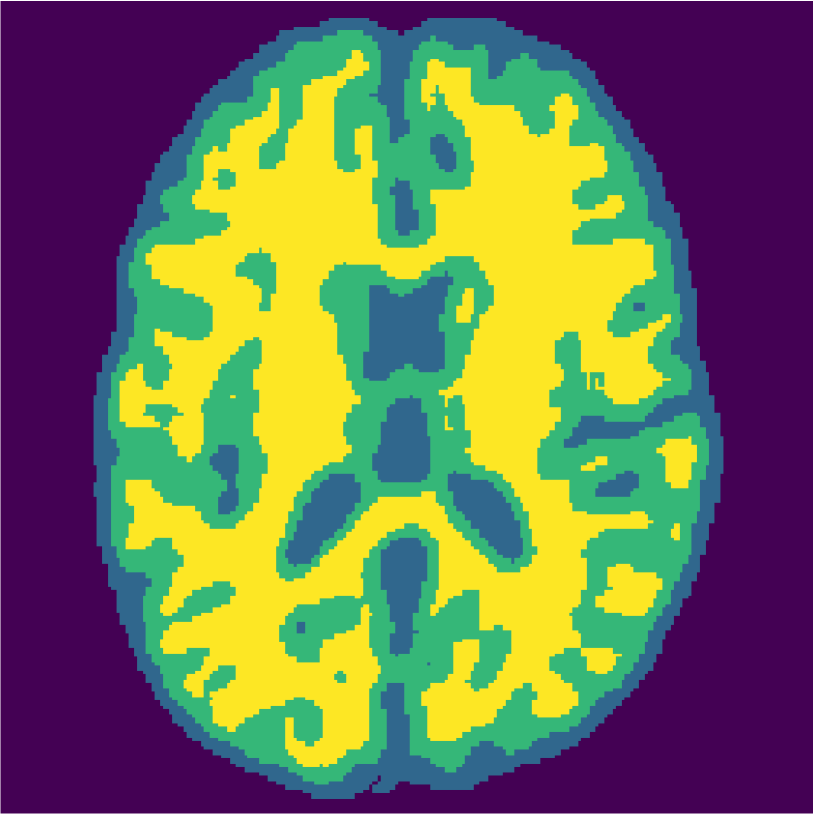

Appendix A describes the nuclear magnetic resonance (NMR) relaxation times for the tissues in the Brainweb anatomical models, for 1.5 and 3.0 Tesla field strengths. The tissues in the anatomical models are grouped into ”background” (BKG), ”cerebrospinal fluid” (CSF), ”gray matter” (GM), and ”white matter” (WM) to compose the ground truth segmentation labels for the simulated scans. The simulations result in images of 256 by 256 pixels, with a 1.0x1.0mm resolution. Figures 5(a) and 5(b) show examples of the Brainweb1.5T and Brainweb3.0T scan of the same subject. For all scans, we used a brain mask to strip the skull.

Figure 6 displays the manually selected patches and their position within the image. For both the source and target classifier, one target patch per tissue is insufficient to achieve good tissue classification performance (2 (top row): 0.631 and 0.613). However, the mrai-net classifier shows considerably better performance (0.223), using only one target patch per tissue. The proxy -distance also drops from near perfect separability (1.88) to near invariance (0.26). Randomly selecting (10 repeats) 1 target patch per tissue (Table 2 (bottom row)), shows worse performance of the mrai-net classifier, for both the classification error (0.250) as well as the -distance (0.41). Suggesting that purposive (information rich) sampling beats random sampling in this case.

Examples of the segmentation results on one of the target test images are shown in Figure 8 for experiment 2.1, Figure 9 for experiment 2.2, and Figure 10 for experiment 2.3. Examples are shown after using 1 target patch per tissue for training, and after using 100 target patches per tissue for training. The results show that only the mrai-net classifier is able to predict a segmentation that approaches the ground truth with only 1 target patch per tissue for training (error for experiment 2.1 = 0.269, experiment 2.2 = 0.403, experiment 2.3 = 0.320), while the source and target classifiers cannot (source error for experiment 2.1 = 0.667, experiment 2.2 = 0.653, experiment 2.3 = 0.435; target error for experiment 2.1: 0.591, experiment 2.2: 0.614, experiment 2.3 = 0.596). After using 100 patches the source and target classifiers can predict a gross segmentation of WM, GM and CSF (source error for experiment 2.1 = 0.213, experiment 2.2 = 0.384, experiment 2.3 = 0.363; target error for experiment 2.1: 0.205, experiment 2.2: 0.368, experiment 2.3 = 0.368), but the mrai-net classifier prediction shows more details and a lower tissue classification error (error for experiment 2.1 = 0.111, experiment 2.2 = 0.276, experiment 2.3 = 0.284).